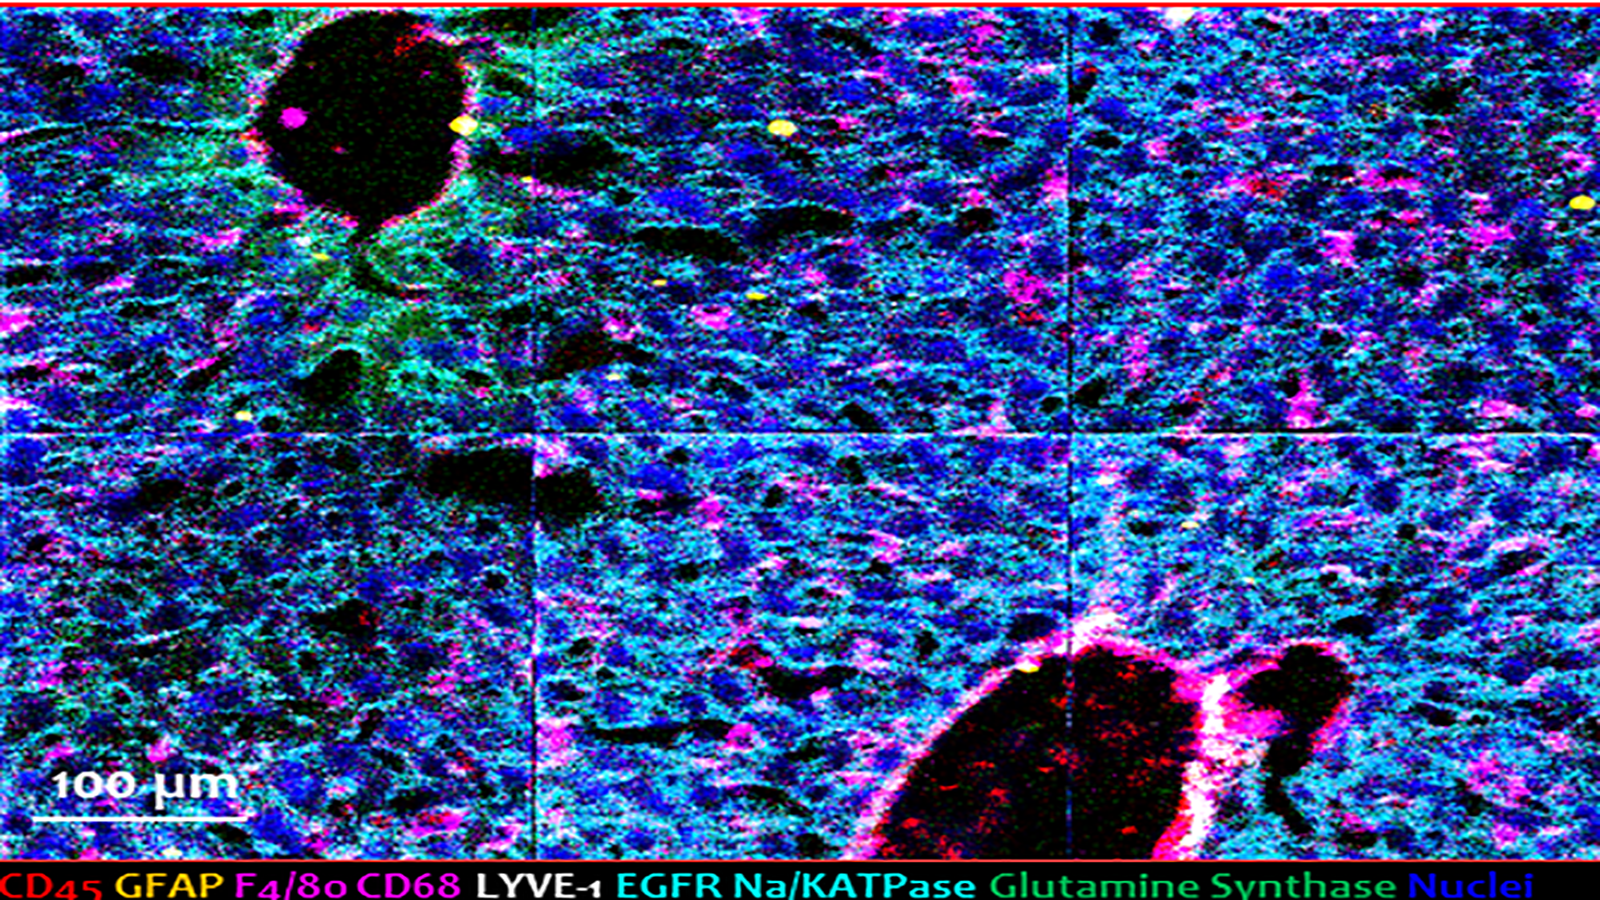

Cell DIVE image of the human heart, courtesy of Liz McDonough of the Ginty lab at GE Research